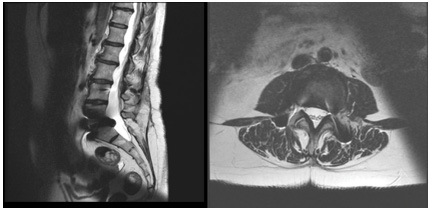

We present the case of a 40-year-old woman who presented with low back pain resistant to analgesics and rehabilitation. She was compensated and had excellent flexion and extension of her spine. The patient had a normal neurologic examination of the lower extremities. Radiographic evaluation revealed good sagittal and coronal balance, despite the co-existing mild thoracolumbar scoliosis. MRI showed Degenerative Disc Disease (DDD) at L4-L5 and L5-S1 (Figure 1A-B). She underwent a lumbar Total Disc Replacement (TDR) at L5–S1with the Charité III prosthesis and Posterior Transpedicular Dynamic Stabilization (PDS) with the Dynesys system at L4-L5 in 2001. Post-operatively, there was significant clinical improvement and the patient went back to work. In 2014, the patient complained of unremitting axial low back pain, aggravated by walking and sitting with increasing difficulty standing and looking straight ahead when walking. Concurrently, polyarthralgia and throcanteritis were also present. This motivated evaluation by Rheumatology for autoimmune disease screening which was negative. Despite being subjected to a new rehabilitation protocol, there was no clinical improvement. X rays showed a degenerative scoliosis with sagittal and coronal imbalance (Figure 2A-B) with multiple discopathies and syndesmophytes through the lumbar and thoracic spine. TDR and PDS were stable and in good position. MRI showed Dark Disc Disease at D11-D12 and from L1-L2 to L4- L5 (Figure 3A-B). The patient underwent a Transforaminal Lumbar Interbody Fusion (TLIF) at L3-L4, PDS removal and T4-L5 posterior fusion in November 2018. At the moment, the patient maintains reported significant improvement in her back pain and reduction in the requirement of analgesic medicines. Physical exam shows good spinopelvic mobility (Figure 4). Radiographs reveal good coronal and sagittal balance and satisfactory position of the total disc replacement and good fusion of the thoracic and lumbar spine proximally (Figure 5A-B) (Figure 6A-B).